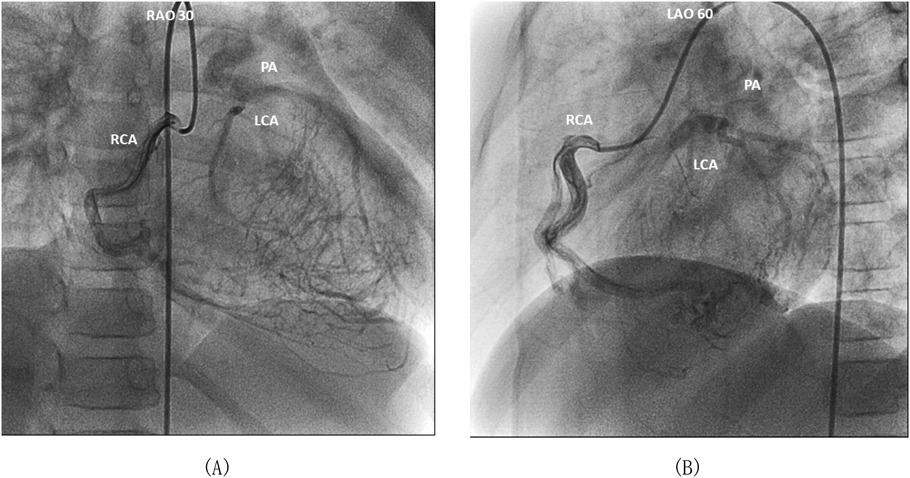

急性期川崎病診療のピットフォール:左冠動脈肺動脈起始症Pitfall in Acute Care of Kawasaki Disease: Anomalous Origin of the Left Coronary Artery from the Pulmonary Artery